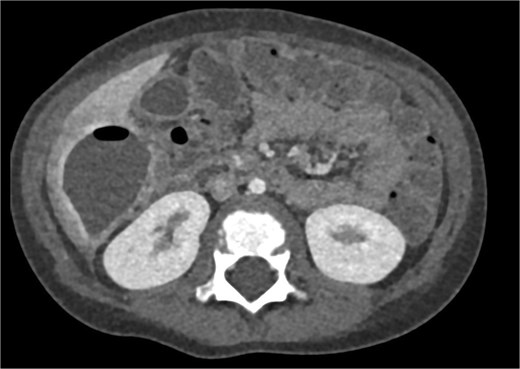

Imaging plays a crucial role in diagnosing appendicitis and its complications. Ultrasound is often the initial modality used, but it may have limited sensitivity in detecting intra-abdominal abscesses, particularly when the appendix is not visualized or when findings are inconclusive [4, 5]. In such cases, contrast-enhanced CT is considered the gold standard, providing detailed visualization of the appendix and associated complications, including abscess formation [2, 4]. In the present case, the initial ultrasound findings suggested an atypical position of the appendix and a pathological fluid collection, but CT imaging confirmed a retrocecal appendix and subhepatic abscesses (Figs 4 and 5), guiding appropriate management.

CT axial view of a subhepatic abscess. Contrast-enhanced capsule and fluid-air level visible.